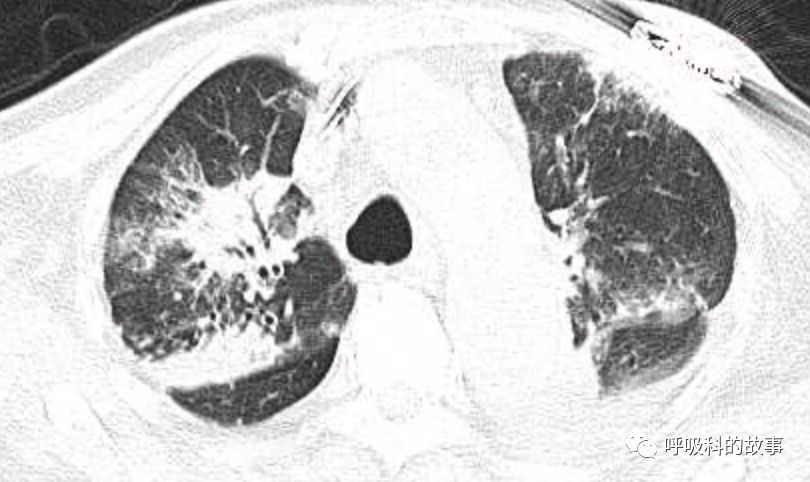

肺部CT如下:

以上的CT给我第一眼的感觉是肺炎,再结合患者有发热和血炎症指标明显增高,肺炎的诊断应该没有问题,但是胸水又是漏出液,结合脑钠肽增高和患者有胸闷气急的症状,心功能不全的诊断也能成立。在某些层面,肺部实变影以内中带为主,还要考虑肺水肿的诊断。入院后给予患者美罗培南抗感染、托拉塞米利尿治疗,以及化痰、雾化处理,患者体温在入院后三天就正常了,入院第五天复查NT-proBNP3390pg/ml;血常规示白细胞 13.5*10^9/L,中性粒细胞81.8%,淋巴细胞13.2%,超敏C-反应蛋白 25mg/L;电解质示钠 160mmol/L,氯 111mmol/L 。虽然炎症指标和心功能指标均有好转,但患者却仍旧精神差,每次查房时仍然表现嗜睡状,家属也反映患者不论白天还是夜晚多数时间不是太清醒。那么问题出在哪里呢?